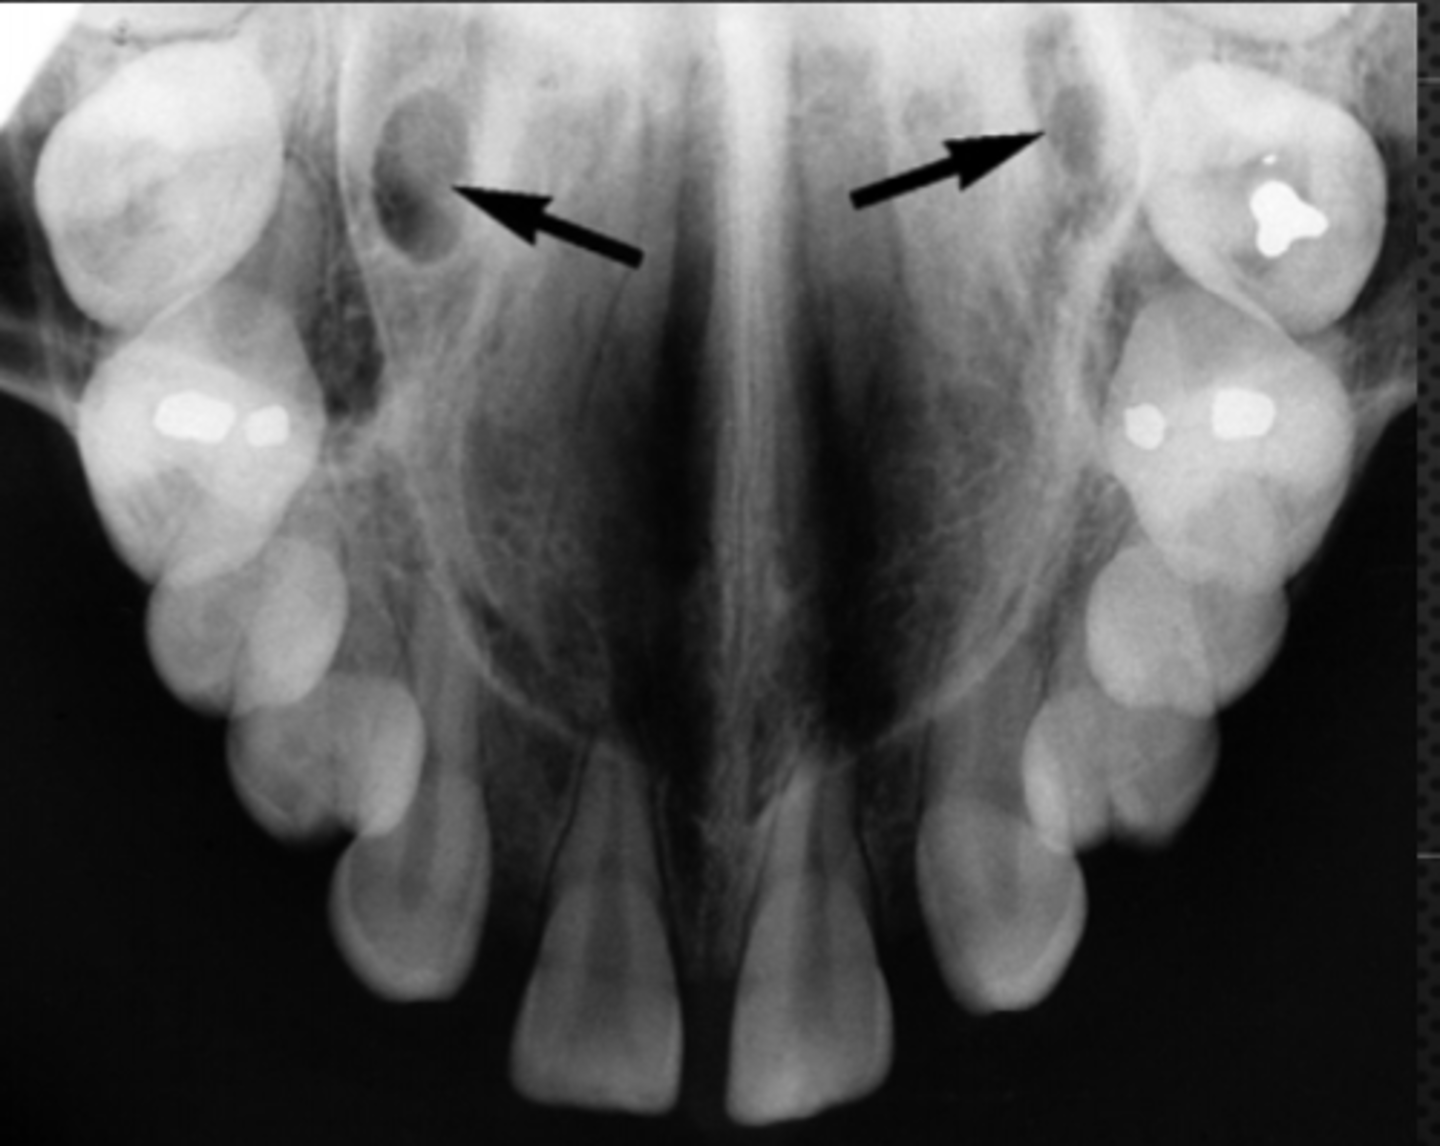

1

Intermaxillary suture (palatine suture)

Identify the structure

2

Anterior nasal spine

Nasopalatine (incisive) foramen

Identify the round, ovoid radiolucent structure indicated by the black arrows.

Superior foramina of the nasopalatine duct

Name the two round radiolucencies indicated.